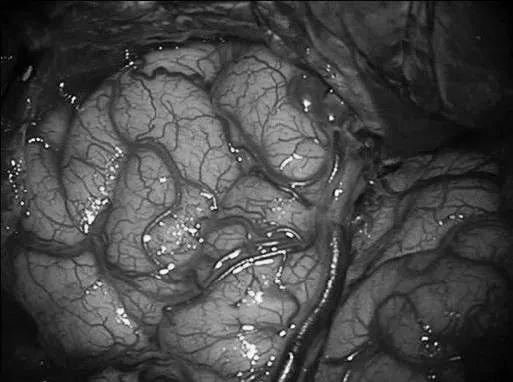

▼左侧翼点开颅,再次手术,显露前颞叶。

▼沿颞下回经原皮层入路达颞角。